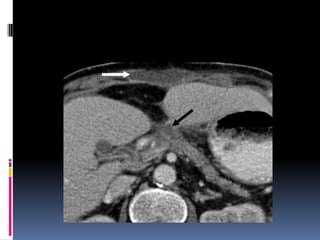

INJURIA HEPÁTICA Grados de severidad RadioGraphics 2009; 29:2033–2053